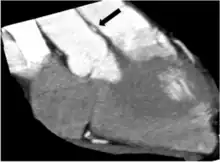

Various imaging tests have a potential to identify coronary artery anomalies. Echocardiography (ultrasound scanning of the heart) is simple, non-invasive and economical. Its use for CAAs screening is limited because its diagnostic sensitivity is highly dependent on the operator's skills and is significantly lower in larger individuals (>40 kg). The diagnostic power of echocardiography is generally poor in most cases after infancy. Especially if clinical suspicion for CAAs is high (e.g. syncope following exertion and/or history of aborted sudden cardiac death). Cardiac magnetic resonance (CMR) is an excellent tool to identify coronary artery anomalies with a significantly higher diagnostic accuracy than standard echocardiography. Compared to CMR, coronary computed tomographic angiography (CCTA) provides more precise assessment of coronary anatomy, course and degree of stenosis, but its clinical use for screening is strongly limited by its cost, the need for ionizing radiation, intravenous contrast and, in many cases, drugs administration. Assessment of severity of stenosis is best achieved by intravascular ultrasound (IVUS) imaging and it should be considered in known carriers of ACAOS-IM or that have symptoms or positive stress test results or are involved in competitive exercises. IVUS consists of cross-sectional imaging of coronary arteries in a catheterization laboratory by advancing a thin probe inside the vascular lumen, obtaining precise in-vivo information about degree of area stenosis in different arterial segments, providing a solid basis for treatment strategies.